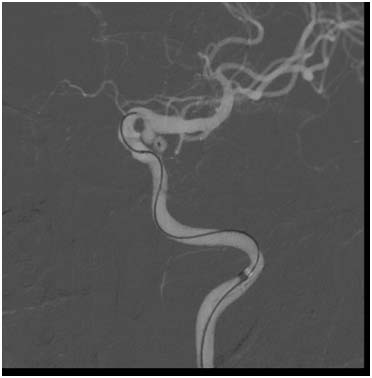

一切准备就绪后,4月3日上午9点,手术在全麻下开始,首先进行脑血管造影,作为金标准检查,这一点相当关键,造影显示动脉瘤的形态和之前的CTA比较有明显的改变,呈现“葫芦”形状,无形当中增加了手术难度,相当于两个动脉瘤!

微导管塑形,一次超选即顺利的到达了动脉瘤底部

在微导管稳定到位后,手术人员逐步填塞弹簧圈,他们先将葫芦远端填实,再回退微导管填近端、封瘤口,最后动脉瘤致密栓塞。